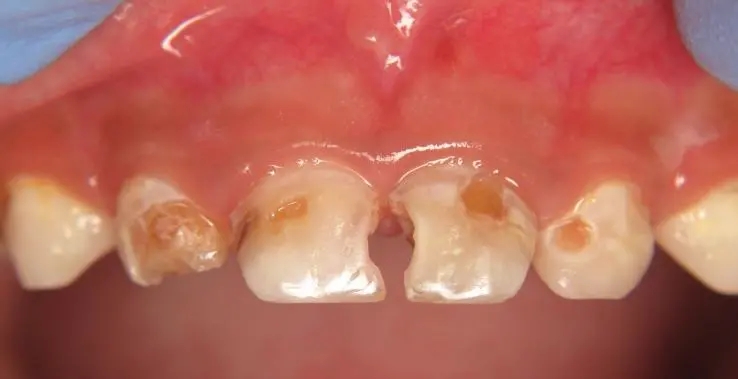

“奶瓶龋”患者,上颌乳切牙的真实照

“奶瓶龋”最初在上颌乳切牙的唇面龈缘处出现白垩色斑点或带状脱矿,而后逐渐向下向旁边蔓延,侵蚀邻近的牙面形成环状龋,呈棕褐色,并最终发生牙冠折断,仅留下残根。导致奶瓶龋的原因: